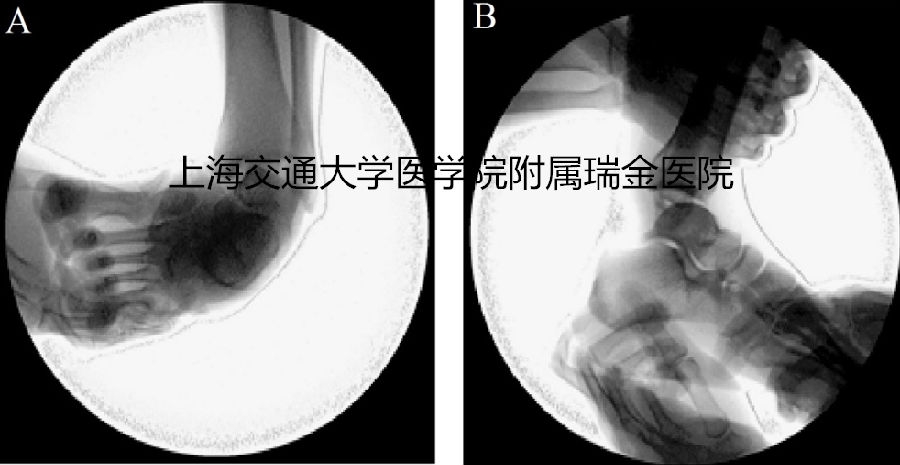

Afterperforming a diagnostic arthroscopy verifyingankle instability (Figure 1), the semitendinosustendon was harvested from theipsilateral affected limb via a two-incision technique (Figure 2) in which the proximalincision was made at the most medial tendon 2 cm above the jointline and the distal incision was made 2 cm medial to thetibial tuberosity. After the 2 ends of the tendon were exposed, the semitendinosustendon was isolated using a specialized tendon stripper, released from thedistal end, extracted from the proximal incision, and finally immersed inphysiological saline until use after being woven withthe 20 absorbable muscle tendon suture (Johnson & Johnson Medical Ltd.Sommerville NJ, USA).

Figure 1 The C-armfluoroscopic examination of lateral ankle instability. A and B represented anterior-posteriorand lateral views.